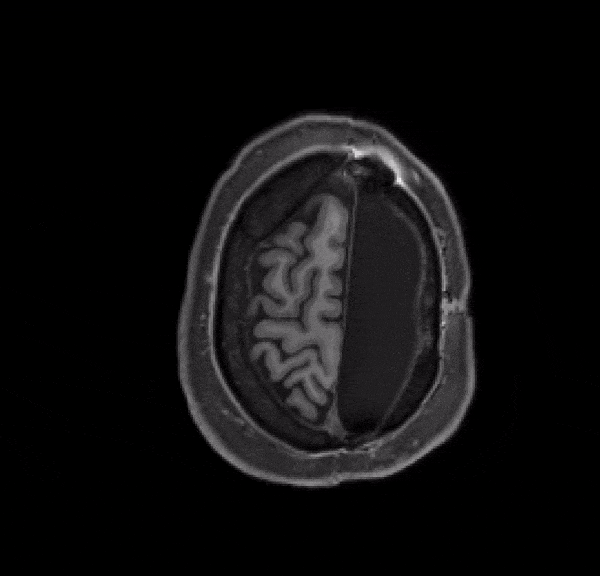

「コンピューターの画面で半分しか脳がないMRIを実際に見てもびっくりです。その画像が、目の前で話をしたり、歩いたり、そしてこの研究に協力してくれている同一人物からのものだなんてね。」

この研究では、安静にしている参加者の脳のMRI画像を撮り、それをきちんと丸ごと残っている通常のものと比較した。

まず明らかになったのは、参加者の半分だけの脳が示すパターンは、完全な脳のそれと非常に似ていることだった。

しかし、もちろん重要な違いもあった。半分だけの脳のネットワーク結合は、普通よりも多かったというのだ。